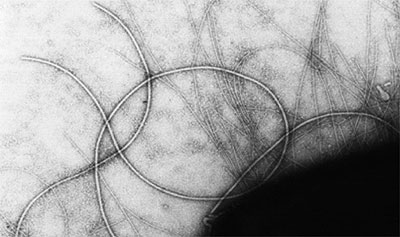

Figure 1: Chrysotile bundle from World Trade Center dust.

Source: USGS Denver Microbeam Laboratory